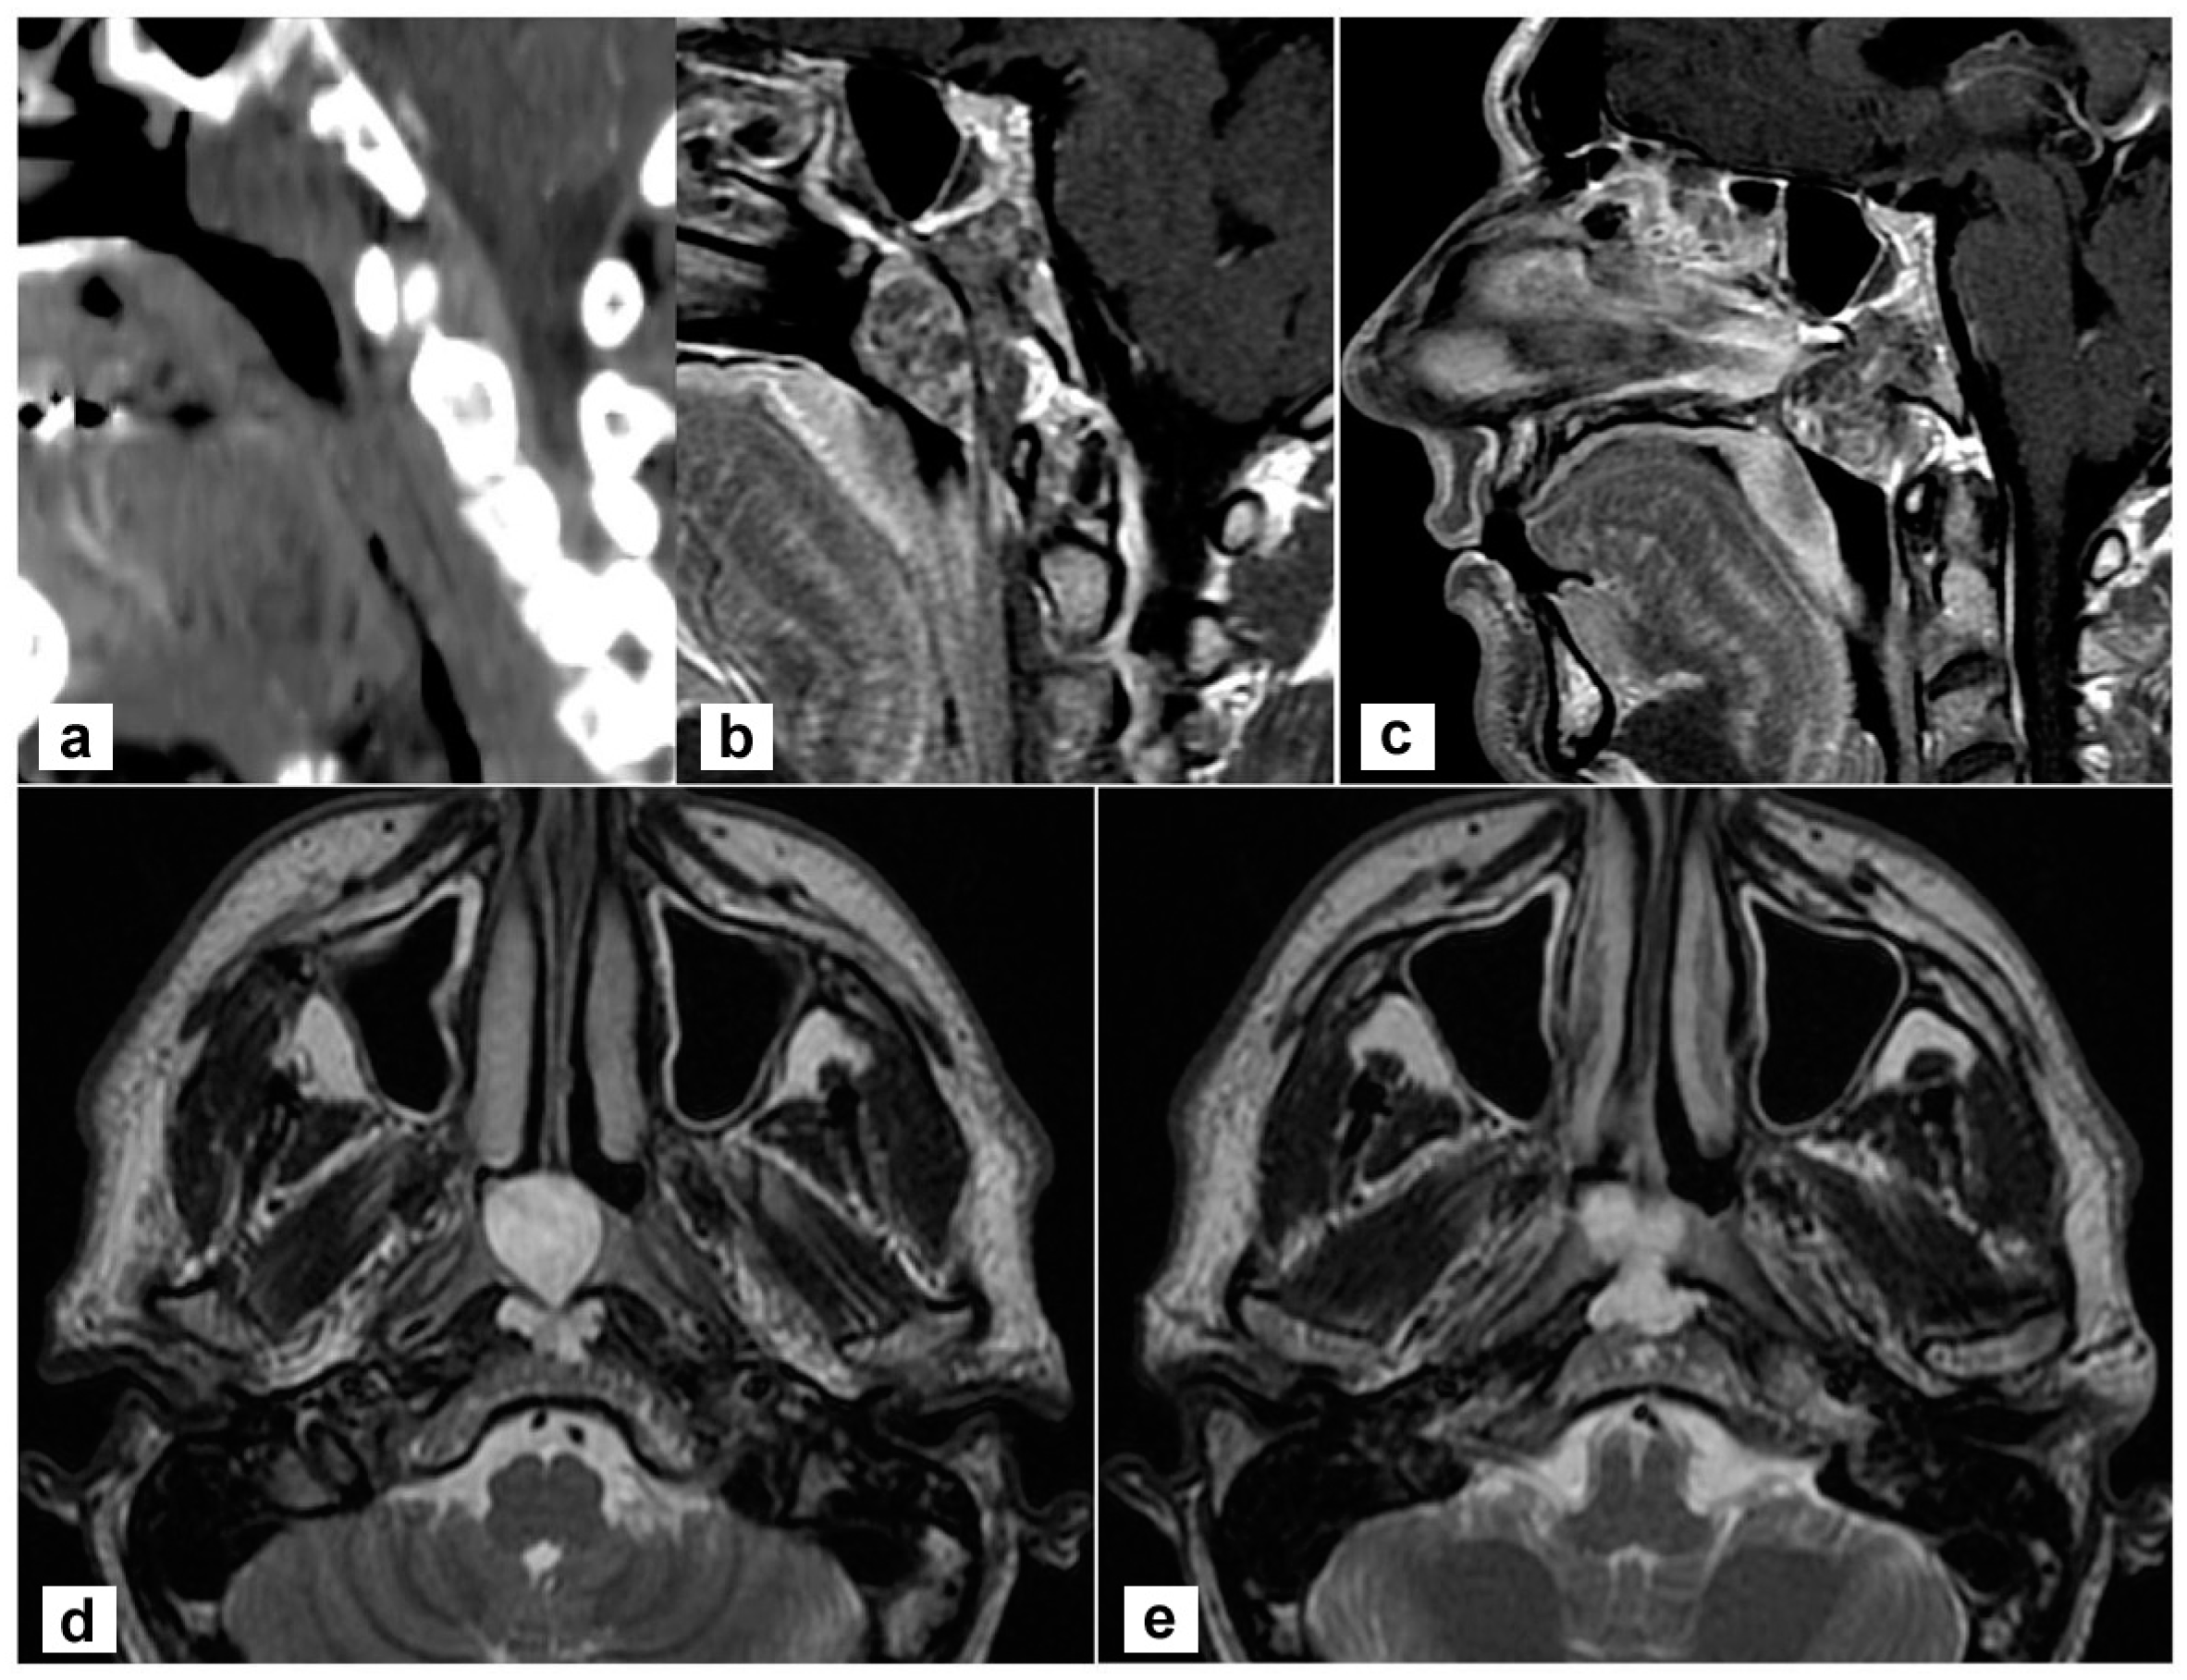

A 45-year-old man complained of persistent nasal obstruction. Nasal endoscopy showed a grey-pink mass filling the nasopharynx and obstructing the choana of both sides. Brain computed tomography (CT) scan showed a lesion of the posterior wall of the nasopharynx eroding the lower clivus on the left side. At MRI the mass was hyperintense on T2 weighted sequences and extended to the lower clivus and prevertebral muscles. No transdural extension was evident (Figure 1). These findings suggested, on the whole, the diagnosis of chordoma.

Figure 1.

Radiological findings of the primary tumour. (a,b) Sagittal view on a paramedian plane on the left side showing the erosion of the upper portion of the lower clivus (a, computed tomography; b, T1-weighted MR sequence with contrast agent); (c) The lesion originates from the clivus and abutt to the clivus obstructing both choane (T1-weighted sequence with contrast); (d,e) the lesion is hyperintense in T2-weighted sequence; the involvement of prevertebral muscles is evident.